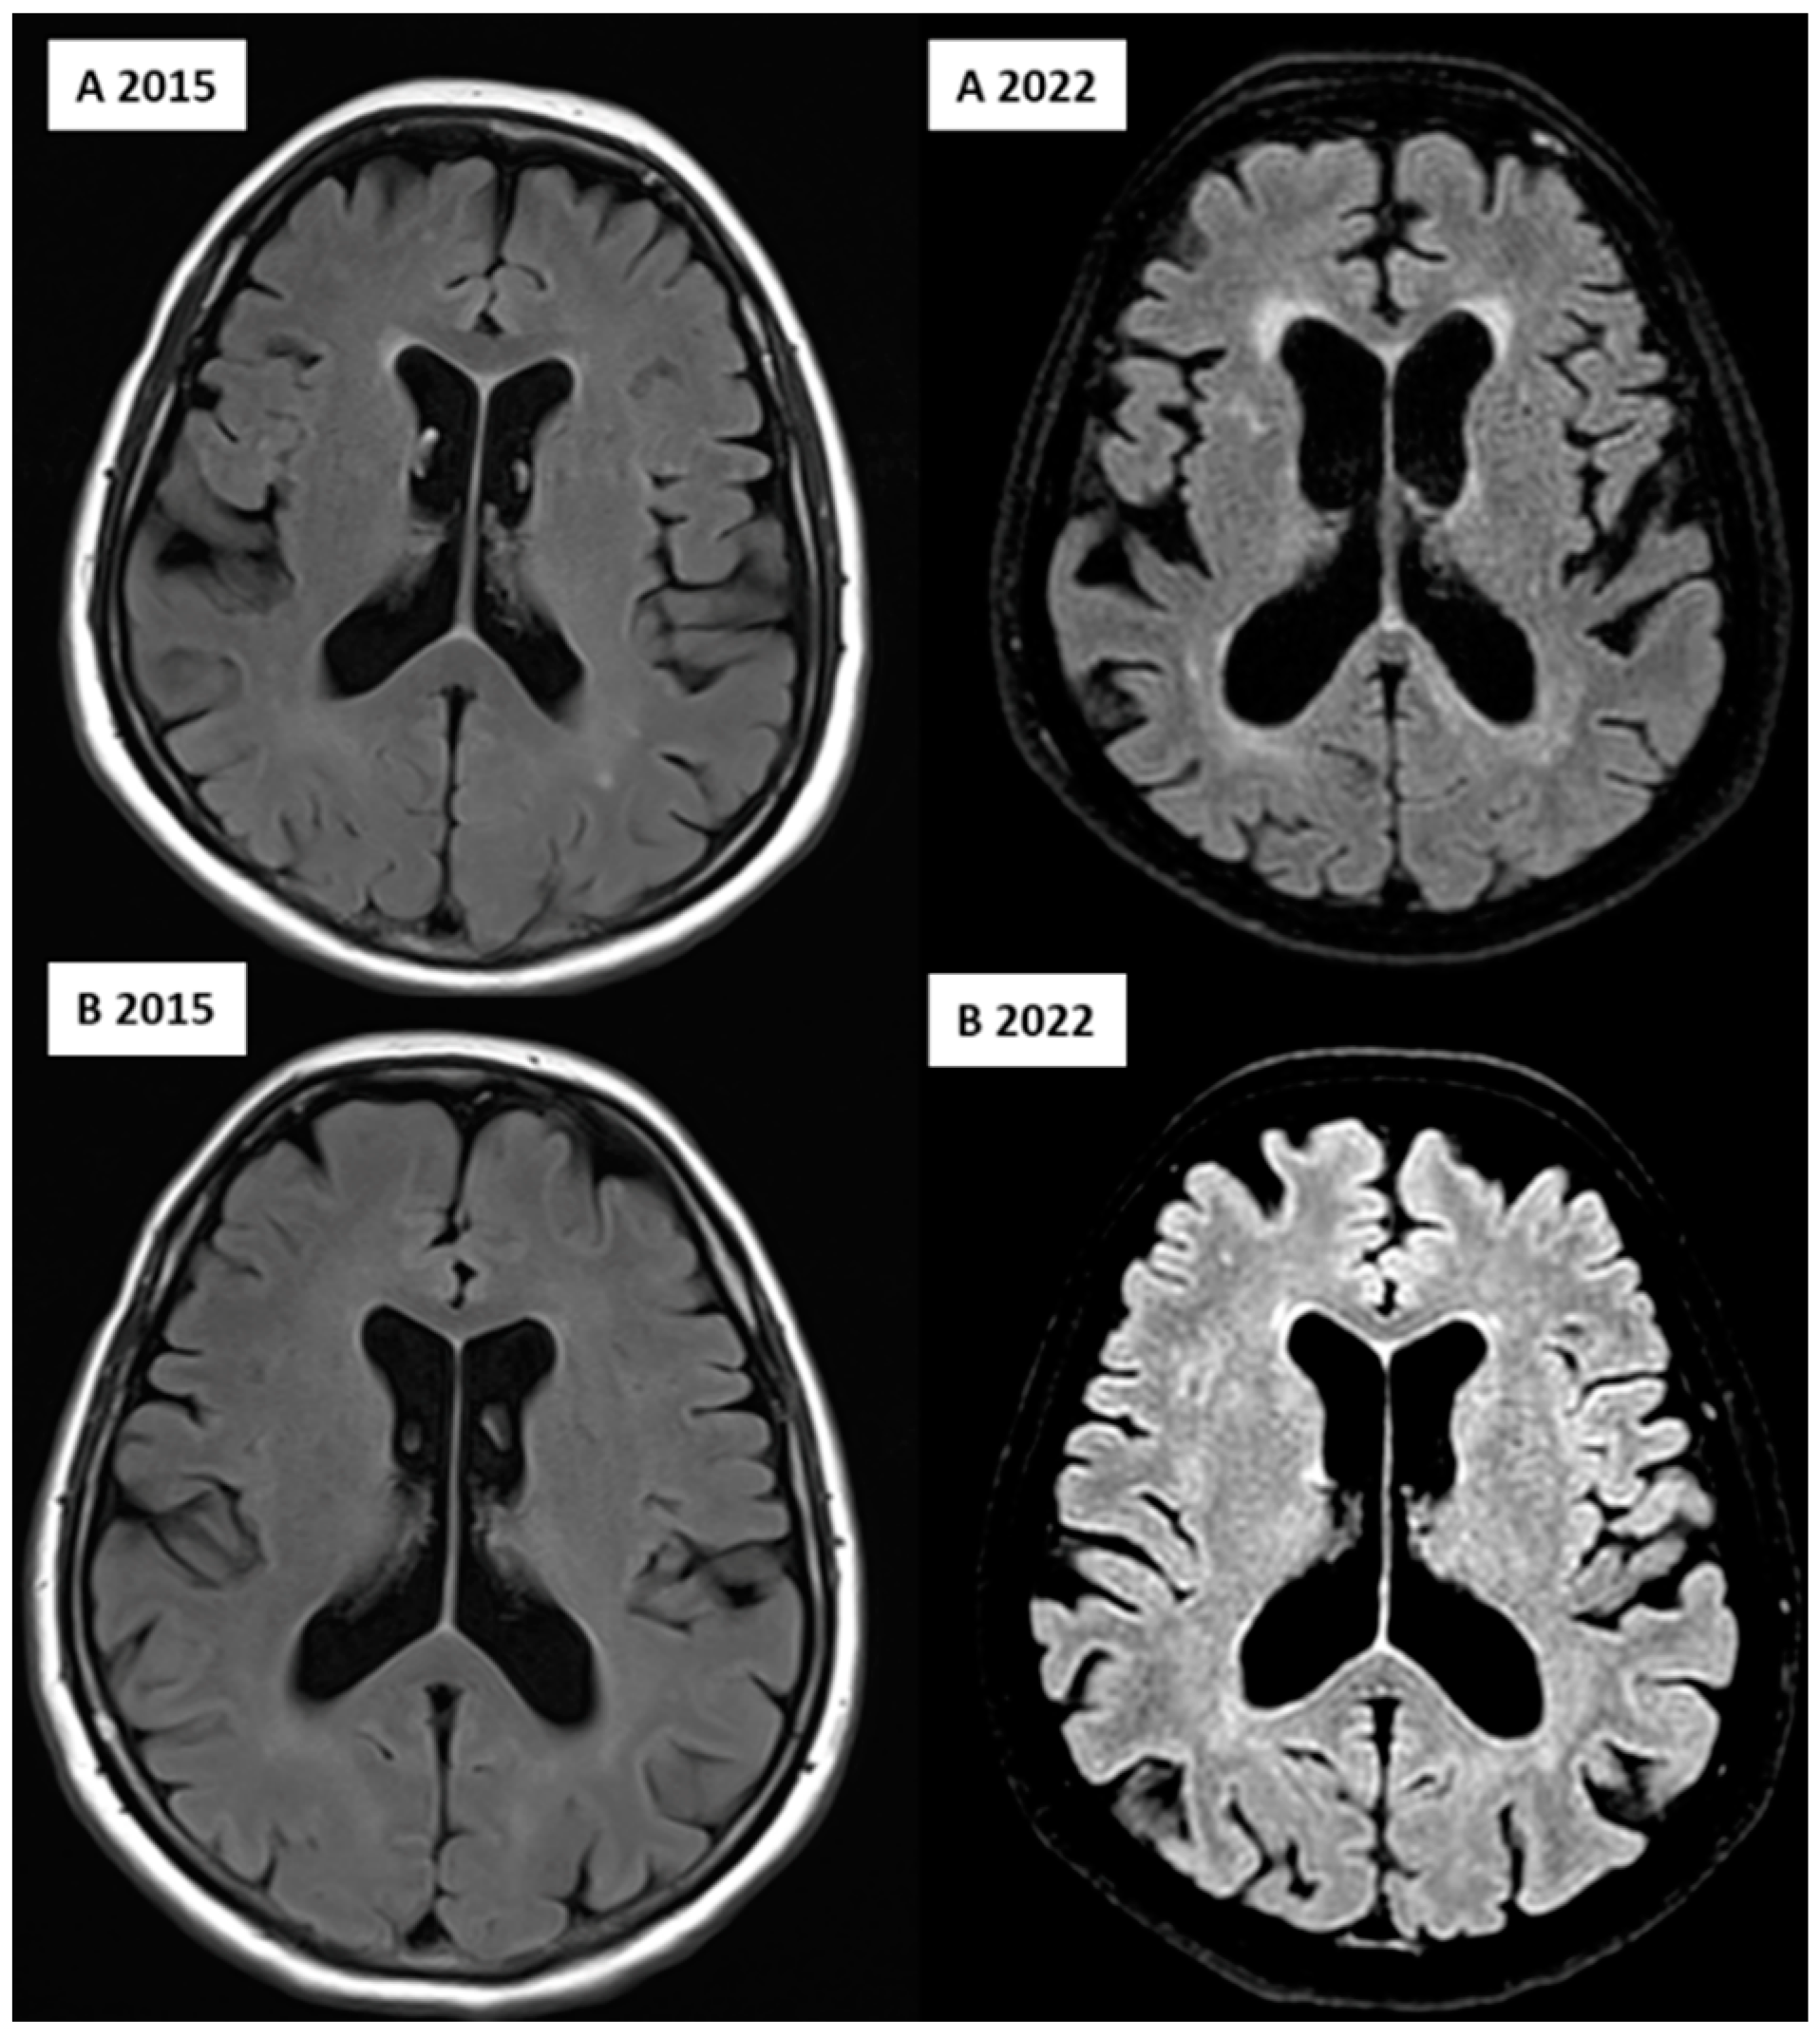

FLAIR image of the affected (A, upper row) and unaffected (B, lower row) twin over 7 years, showing the progression of the WMHs in the deep and periventricular regions and ventricular dilation, indicating global cerebral atrophy; image from the Semmelweis University Medical Imaging Centre.

Concerning neuroimaging, we detected a left cerebellar lacunar stroke and signs of PSP (midbrain atrophy) in the affected twin; signs of normal-pressure hydrocephalus (NPH) were also observed. However, the latest brain MRI certified questionable signs of a possible beginner PSP, a narrow oedematous signal disorder in the cerebellar tonsils, and possible signs of normal-pressure hydrocephalus in the unaffected twin (Figure 1 and Figure 2).

Many studies have reported various structural neuroimaging findings in T1- weighted, T2-weighted, and FLAIR images, including midbrain atrophy, atrophy of the superior cerebellar peduncle, and frontal and parietal cortical atrophy, which were present in the affected twin. Moreover, dilatation of the third and fourth ventricles and the aqueduct of Sylvius was also observed, which was present in the twin pair, with dominance in the affected twin. In addition, atrophy of the subthalamic nucleus is the most typical trait of PSP. The most characteristic pathological finding is the atrophy of the midbrain, which is demonstrated by the hummingbird sign as a result of rostral midbrain atrophy observed on mid-sagittal images, which was observed in the affected twin [6,36]. Interestingly, MRI signs of possible beginner PSP were suspected in the MRI imaging for the unaffected twin despite them being clinically asymptomatic, including narrow edematous signal disorder in the cerebellar tonsils and possible signs of NPH. The WMH analysis demonstrated remarkable differences between the twins, especially in the total, periventricular, and juxtacortical WMH lesion volume, which were higher in the PSP-affected twin. In addition, a remarkable decrease in brain volumes, mainly in total gray matter and frontal lobe volume except for temporal lobe volume, was observed. In the affected twin, a left cerebellar lacunar stroke was also observed, which referred to a vascular (possibly atherosclerotic) origin.